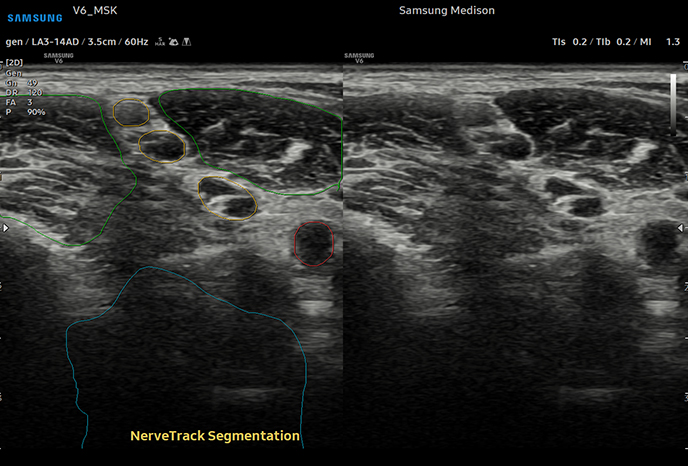

02최첨단 정밀 검사대학 병원급 하이앤드 초음파 장비와 다각적 검사 시스템

심장 질환 진단에서 가장 중요한 것은 ‘심장의 상태를 얼마나 정확하게 볼 수 있느냐’입니다. 저희 센터는 대학병원급 하이앤드 초음파 장비를 도입하여, 실시간 3D 렌더링으로 정밀 진단이 가능하며, 심장의 구조·혈류·기능을 실시간 고해상도로 관찰합니다.

미세한 판막 움직임, 혈류 속도 변화, 심방·심실 크기와 수축력까지 정밀하게 분석할 수 있어, 심장질환의 조기 발견과 치료 계획 수립에 큰 차이를 만듭니다.